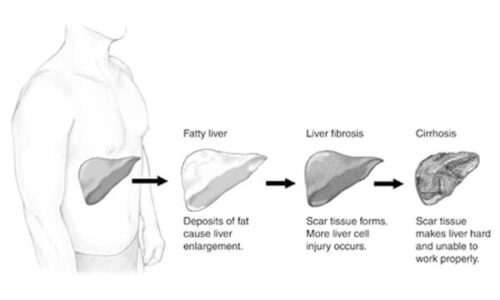

- suffer from certain medical conditions, such as hepatitis, liver cirrhosis, gallstones, diabetes, a parasite in the liver (liver flukes), and HIV